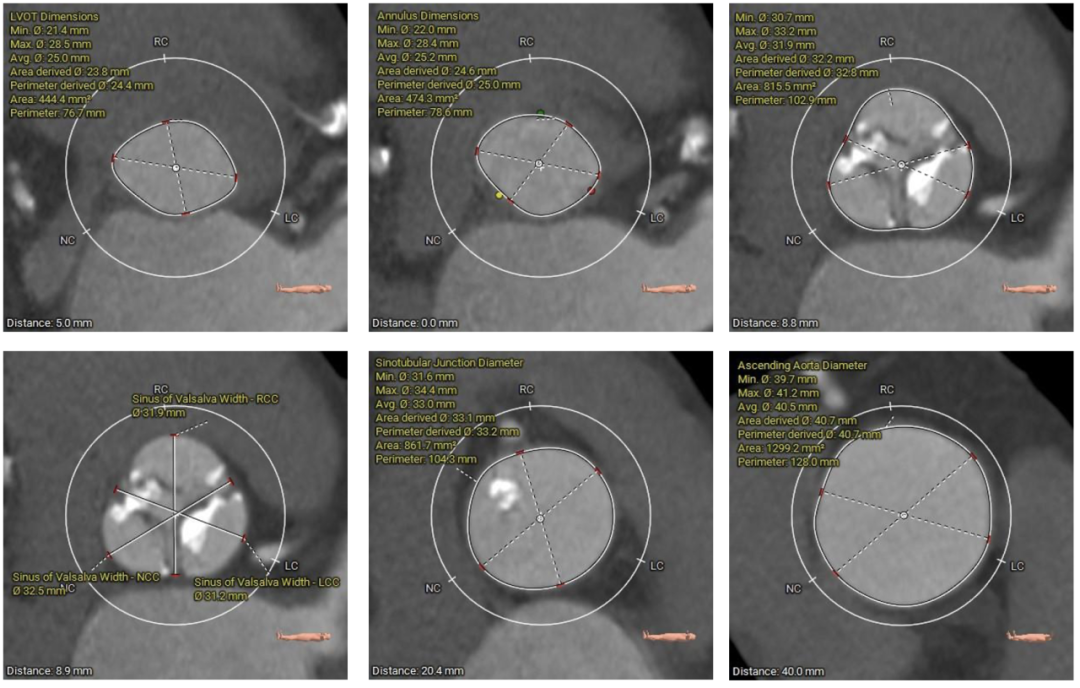

在完成术前CT扫描后发现,李阿姨入路腹主动脉严重扭曲、横位心、右冠窦无冠窦钙化融合且冠脉开口位置相对较低,左冠瓣叶冗长,术中冠脉闭塞风险高,这些不利因素均会明显增加手术的难度和风险。为此,医院迅速启动多学科协作机制,由医务处牵头,联合心血管科、麻醉科、重症医学科、血管外科、胸外科等专家团队展开会诊。经过反复讨论,专家团队最终决定采用国际先进的治疗方案一一经导管主动脉瓣置换术(TAVR)。这种微创手术无需开胸,只需通过血管穿刺即可完成瓣膜置换,极大降低了手术风险。为确保万无一失,心血管科团队还通过线上会议邀请国内知名专家对病例进行远程讨论,制定了精细化手术方案,包括入路解决方案、冠脉保护策略、术中应急措施以及术后康复计划。

▲主动脉根部测量

患者病理特点

1. 冠脉高风险:三窦三叶式主动脉瓣,右无之间钙化融合,钙化分布不均。右无融合脊会把瓣架往左冠脉开口方向推挤,并且左冠瓣叶相对冗长,大大增加了冠脉阻挡的风险。

2. 腹主入路折角:双侧入路血管走形良好,整体入路血管条件一般,腹主动脉可见扭曲,经过测量33cm可以正好通过迂曲部位,也提前备好45cm长鞘,以防血管损伤。

3. 瓣膜通过性:由于横位心及大弯侧有融合脊形成台阶,瓣膜输送器通过会受影响,预备同侧snare圈套,以防无法通过。